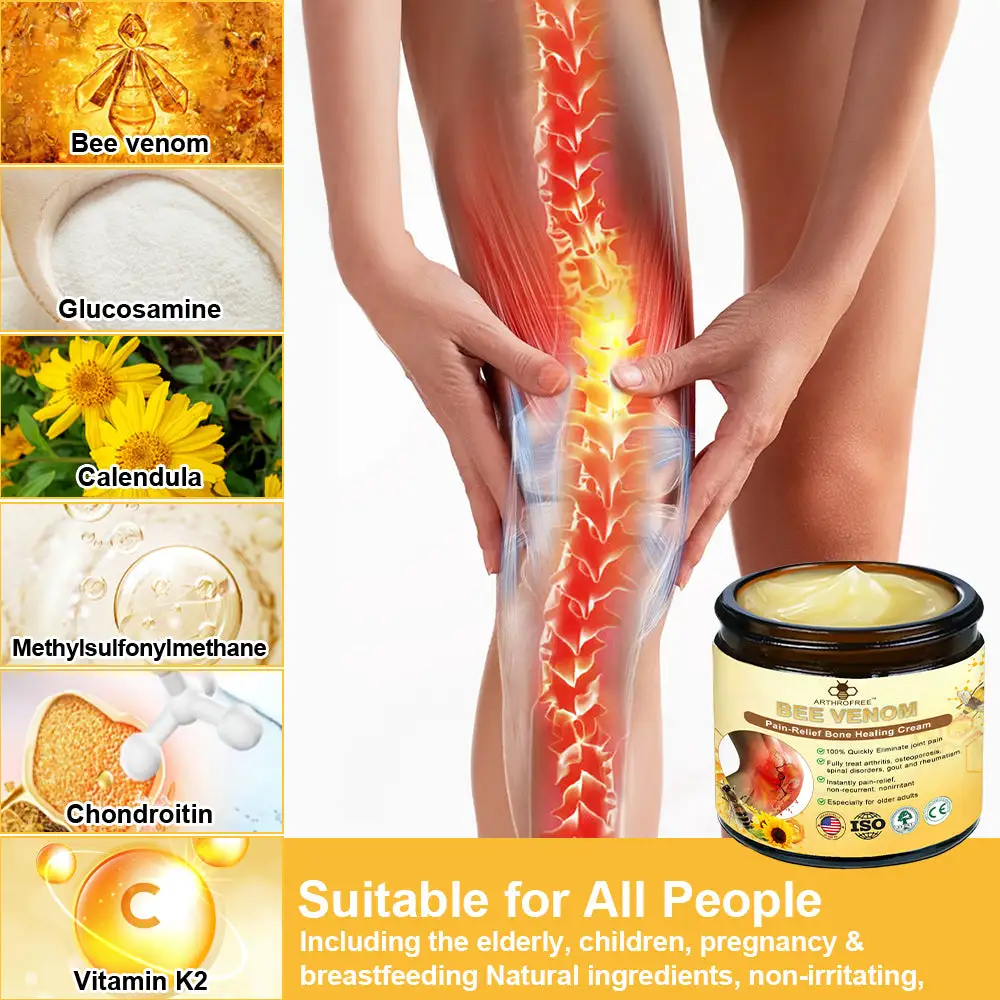

Bee Venom is a toxic secretion from bees that comprises a variety of biologically active compounds. The primary ingredient in Bee Venom is melittin, a bioactive protein produced by bees’ venom glands. Melittin possesses potent anti-inflammatory and analgesic properties, effectively alleviating arthritis-related pain and swelling.

In addition to melittin, Bee Venom contains enzymes, amino acids, sugars, lipids, and vitamins, which contribute to joint tissue repair, enhanced joint elasticity, and improved mobility. Enzymes like kininase and phospholipase A2 present in Bee Venom promote blood circulation and increase nutrient delivery to joint tissues, facilitating joint repair and regeneration.

Melittin‘s anti-inflammatory action reduces the inflammatory response in arthritis, thereby diminishing joint pain and swelling, and enhancing joint flexibility. Beyond its anti-inflammatory and pain-relieving effects, Bee Venom also offers antibacterial, antitumor, cardiovascular protective, beauty, and anti-aging benefits.

When applied topically, Bee Venom interacts with pain perception receptors and inflammatory pathways in the skin. This interaction can modulate inflammatory processes, potentially reducing the release of pro-inflammatory molecules that contribute to joint and bone swelling.